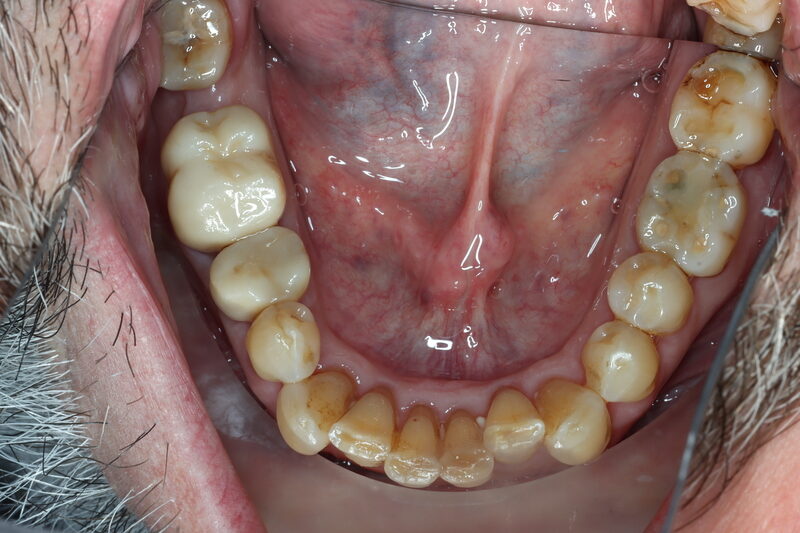

Case 15 – Multi Disciplinary

Salvage of LR56